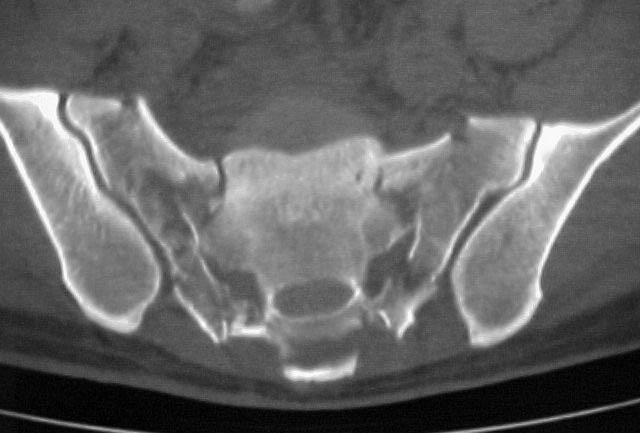

A 28 year old male jumped from the 4th floor on 11-25-2000 sustaining an L1 burst fracture that has been fixed anteriorly by the neurosurgeon with a strut between T12 and L2. A Kaneda device was placed anteriorly as well. My concern is the pelvic ring injury. There are bilateral sacral fractures through the foramen and a transverse element through the sacrum between S2 and S3. the lower part of the sacrum is displaced forward. Anteriorly there are right superior and inferior pubic rami fractures.

"H-shaped" sacral fractures are the combination of a "U" with associated bilateral pelvic ring injuries...analogous to a "Y" with associated bilateral ring injuries...fortunately, rarely are both hemi-pelves clinically unstable.

Also, please note that the caudal sacral component is not displaced anteriorly...this is the stable component of the sacral injury which remains attached to the uninvolved portion of the pelvic ring. The spinal segment is the unstable/displaced component.

Realize that the cervico-thoracic-lumbar-upper sacral segment is the unstable and displaced component.